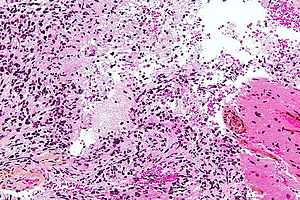

| LM | astrocytic differentiation, nuclear atypia, necrosis, microvascular proliferation, +/-pseudopalisading necrosis |

Microscopic

Features:

- Astrocytic tumour with:

- Nuclear atypia.

- Necrosis.

- Endothelial proliferation (AKA microvascular proliferation).

- +/-"Pseudopalisading necrosis" - tumour cells lined-up like a picket fence around necrotic areas.